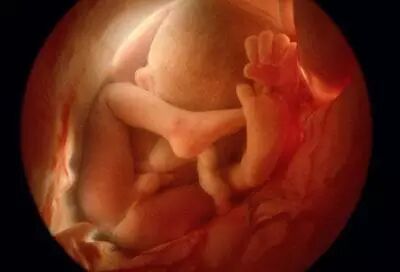

三个月:

胎儿的身体为7-9厘米,体重约20克,重要的是已长出鼻子、嘴唇四周、牙根和声带等,和以前比,更象人脸了,眼睛上已长出眼皮。